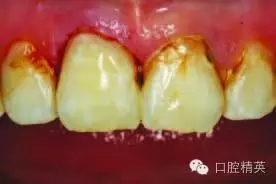

圖2:排齦,去除尖銳和薄弱的釉質(zhì)邊緣

局部麻醉后,先行右上中切牙去腐備洞。使用排齦線暴露齦下齲壞。

使用330-鎢鋼車針去除尖銳和薄弱的牙釉質(zhì)邊緣,開敞釉質(zhì)洞緣(圖2)。